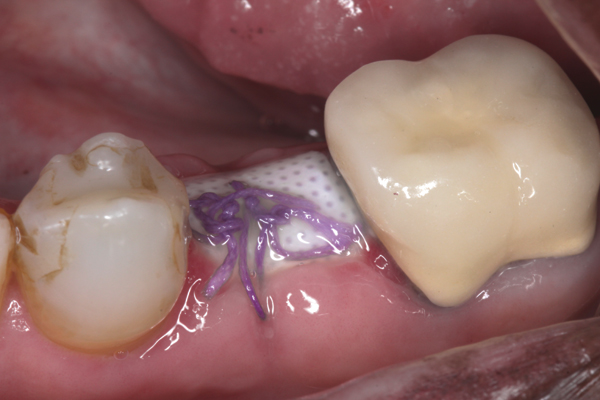

Fig 8. At 4 weeks postoperative, the barrier has been removed, exposing osteoid tissue.

Figure 8

Fig 9. At 8 weeks postoperative, the ridge was keratinized.

Figure 9